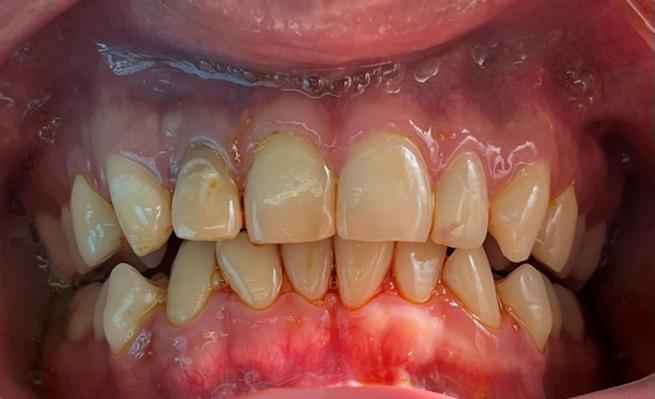

Tratamiento combinado de un quiste radicular de larga data: A propósito de un caso clínico

Combined treatment of a long-standing radicular cyst: A clinical case report

Javier BorisAdrián Burgos, Johanna Valentina Virreyra Bloomfield..........................................................133-142

Issuu converts static files into: digital portfolios, online yearbooks, online catalogs, digital photo albums and more. Sign up and create your flipbook.